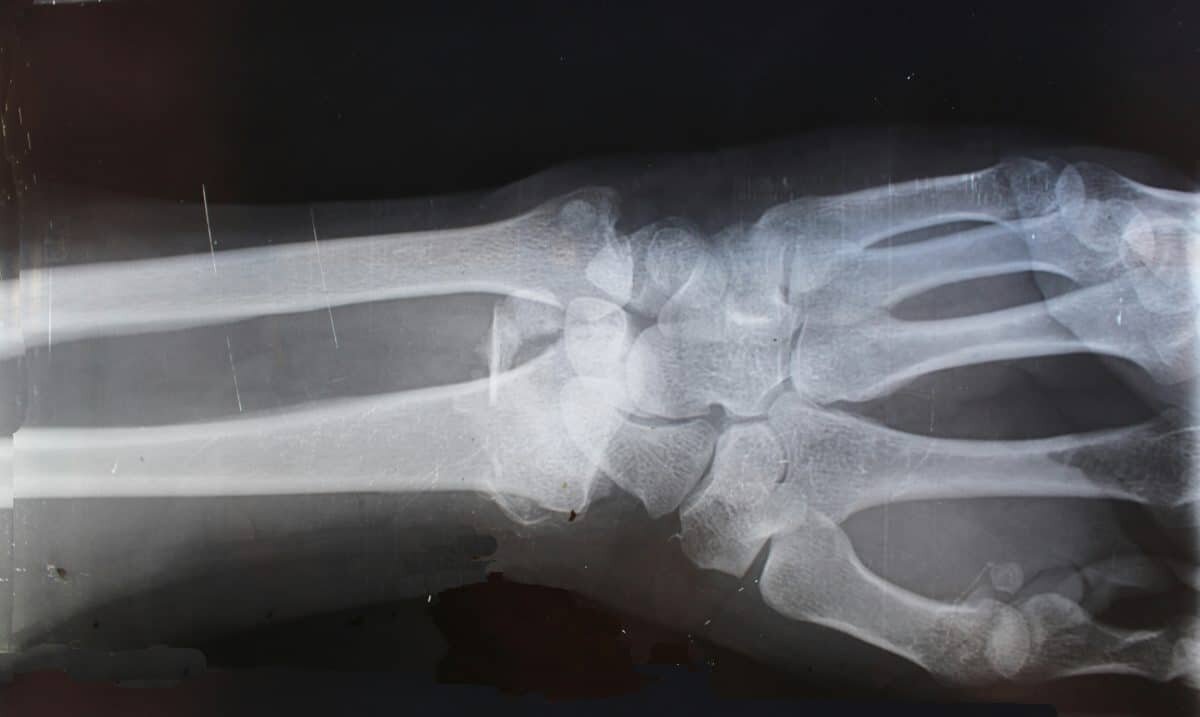

Найдена потенциальная защита от редкой болезни суставов / ©

Найдена потенциальная защита от редкой болезни суставов / © Cara Shelton, unsplash.com📷